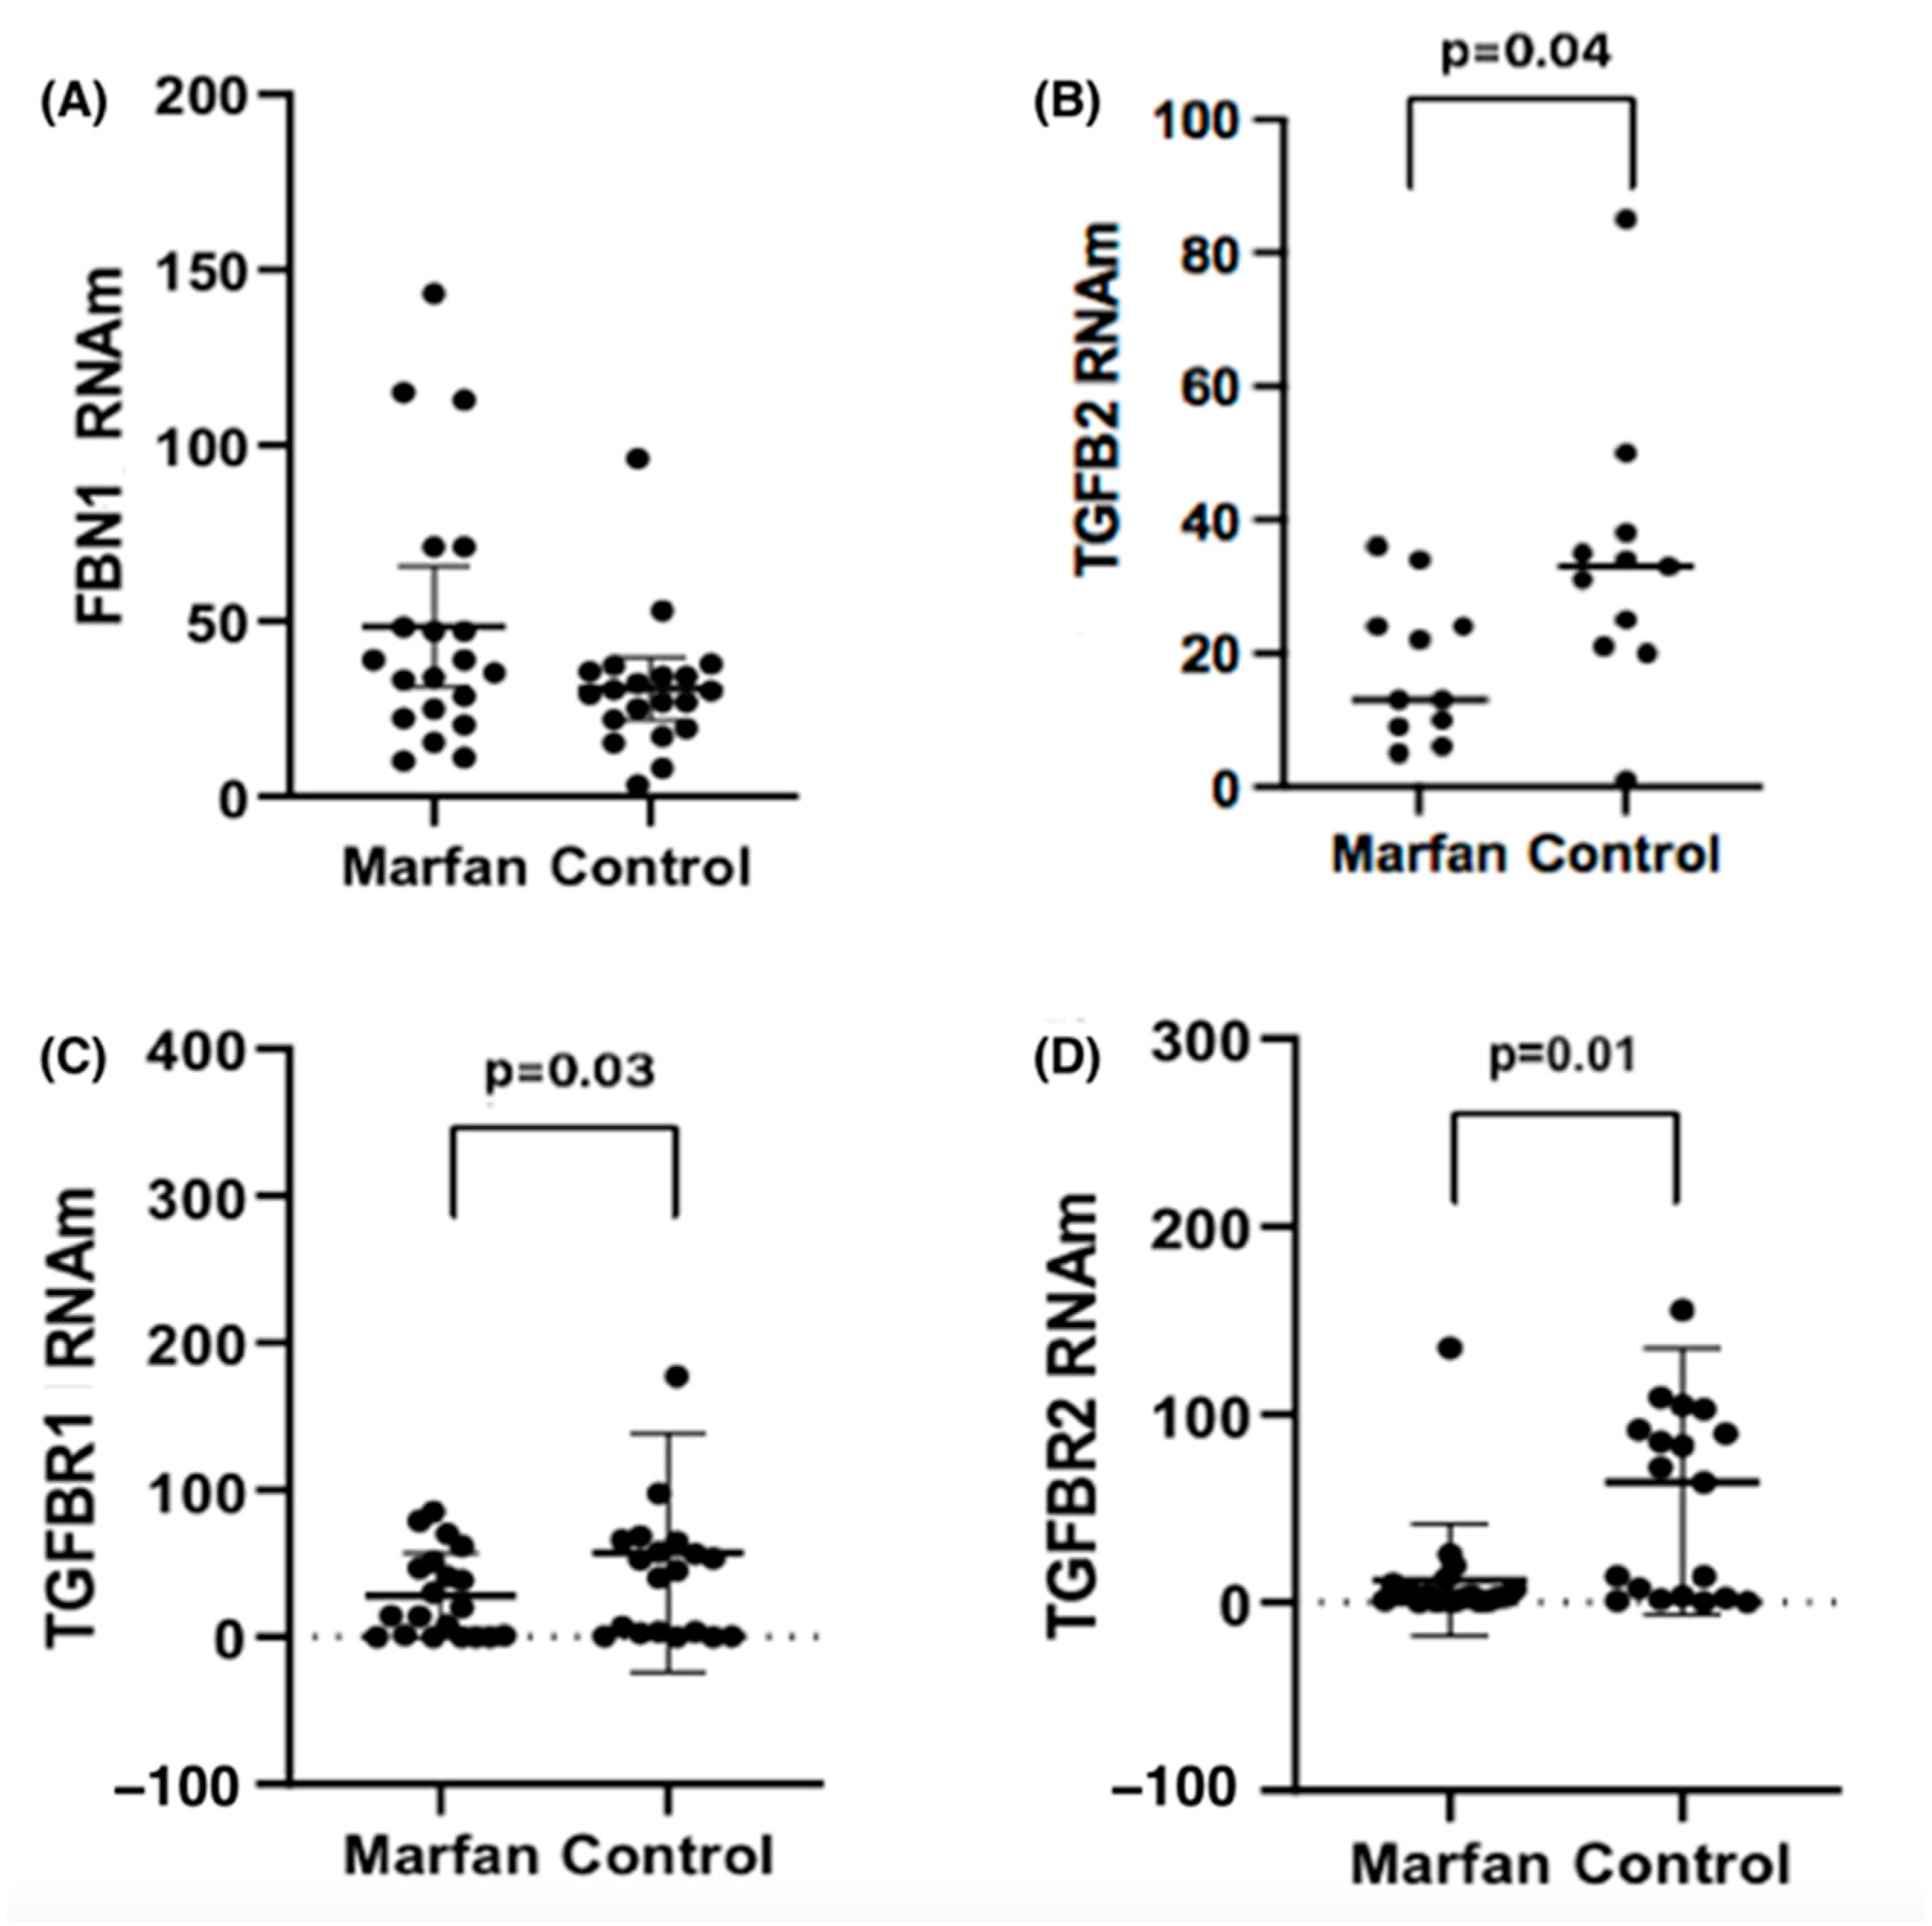

2.3. FBN1, TGFβR1, TGβR2 and TGFβ2 mRNA Level Expression

3. Discussion